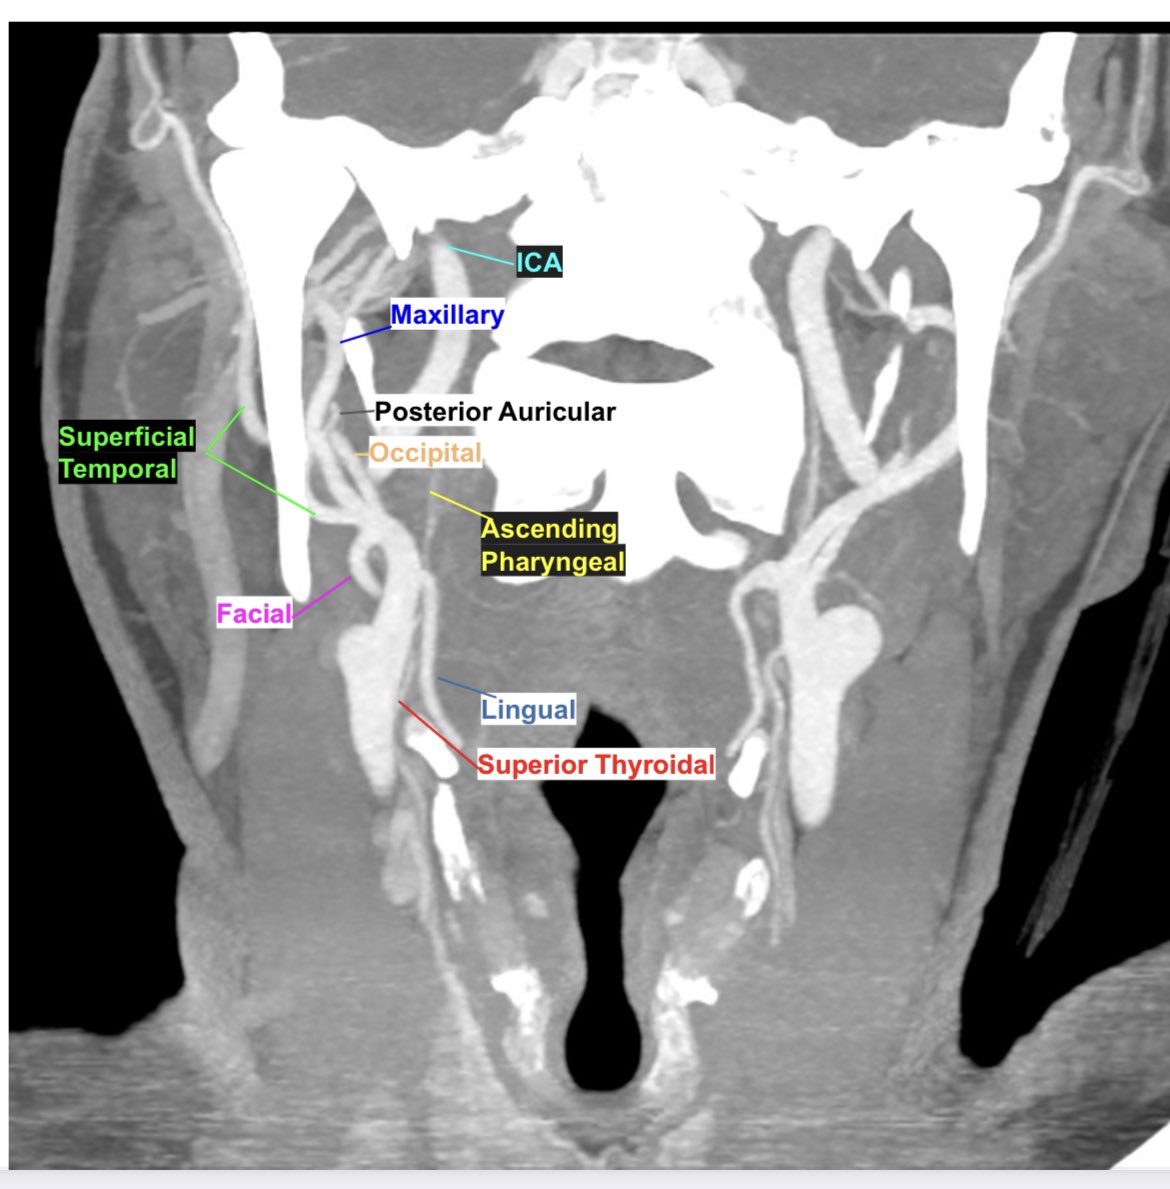

Remember the ECA branches with the mnemonic FALS MOPS to remember the first and second set of branches. While the mnemonic is not in the order of the ECA branches, one can then label the branches based on where they are headed on the CTA 🙃#mightwork #Neurorad #radres #MedEd

learnneurorad's tweet image. Remember the ECA branches with the mnemonic FALS MOPS to remember the first and second set of branches. While the mnemonic is not in the order of the ECA branches, one can then label the branches based on where they are headed on the CTA 🙃#mightwork #Neurorad #radres #MedEd